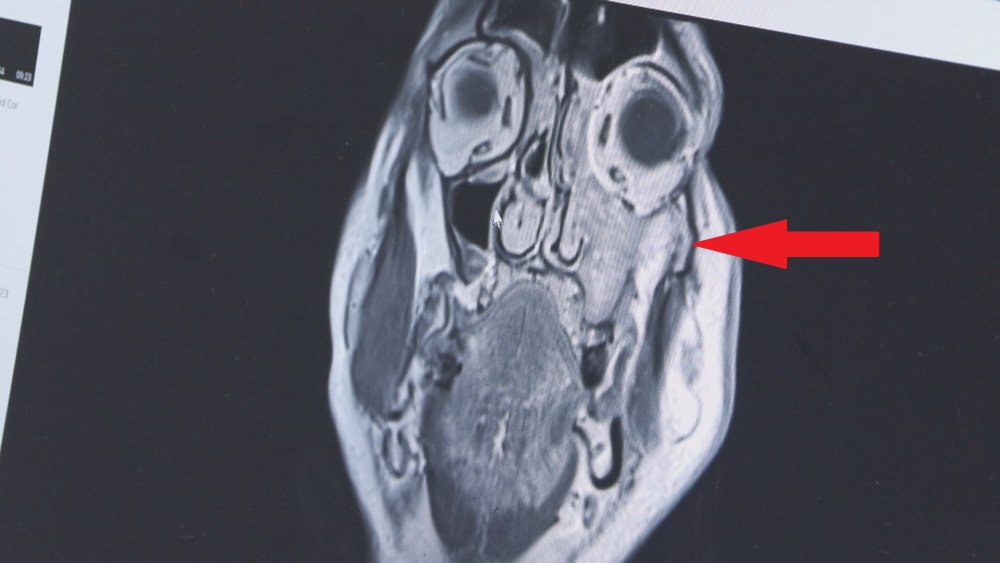

Prof. Dr. Apuhan, şu bilgileri verdi: "Hastamız diş yakınması nedeniyle başka bir merkezde diş hekimine gidiyor. Oradan bize yönlendirildi. Endoskopik olarak muayene ettik ve burnun sol tarafında bir kitle ile karşılaştık. Daha sonra yaptığımız görüntüleme tetkiklerinde yüzün sol tarafında maksiller ve etmoid sinüs dediğimiz bölümü dolduran, göze ve beyin dokusuna kadar uzanım olan bir kitleyle karşılaştık. Ameliyatta özellikle sol tarafta damak bölgesinin göze ve beyne yakın bölgelerini de temizledik. Gözü koruduk. Tümörün geliştiği anatomik bölgenin karmaşık olmasından dolayı hastalık çok geç fark ediliyor ve başka hastalıklarla karıştırılabiliyor. Bizlere de çok geç ulaşıyorlar. Özellikle tek taraflı burun tıkanıklığı, kanaması olan, yüzün bir tarafında uyuşma hissi, şişlik, yüzde asimetri, geçmeyen baş ağrısı gibi şikayetleri olan hastaların vakit geçirmeden mutlaka KBB hastalıkları ve baş boyun cerrahisi uzmanına gitmesini öneriyoruz"

Maksiller sinüs yani yanak bölgesinde çıkan tümörlerin sinüzitle çok karıştırıldığına dikkat çeken Prof. Dr. Apuhan sözlerini şöyle noktaladı: "Göze çok yakın olduğu için görme ile ilgili yakınmalar da eklenebilir belirtilere. Biz KBB hekimleri sinüzitle beraber altta bir kanser dokusu var mı yok mu mutlaka değerlendiririz. Maalesef bu hastalık çok çabuk boyna ve vücudun başka bölgelerine yayıldığı için, boyun diseksiyonu dediğimiz kesi ile ameliyatı tamamlıyoruz. Bu hastamızın da sol tarafına, boyna da yayılmıştı, boyundaki lenf bezlerinde yer alan kanser dokularını da temizledik. Biraz daha geç gelmiş olsaydı göze ve beyin dokusunun içerisine kadar uzanacaktı tümör. Sol yanağında geniş bir rezeksiyon yaptığımız için (tümörü çıkardığımız için), kozmetik deformite olmasın diye oraya protez hazırladık ve birkaç gün içinde o yerleştirilecek. Ayrıca ameliyat sonrası bir süre de radyoterapi alacak"